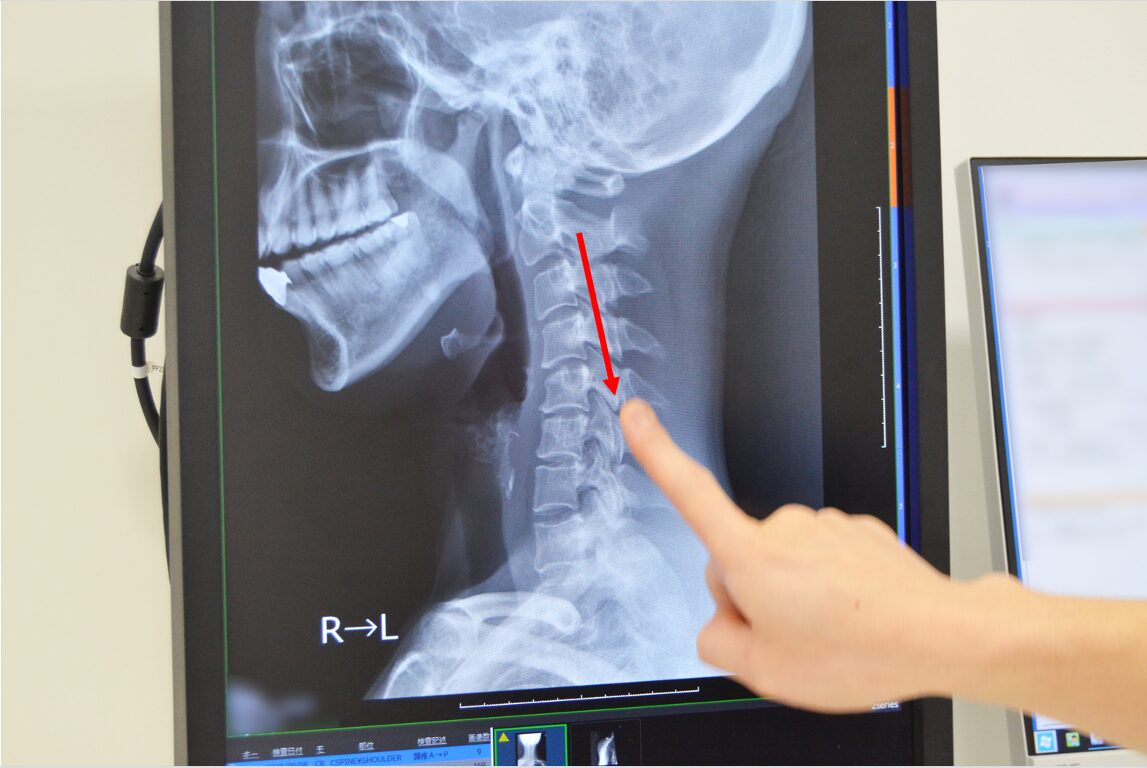

別のレントゲン画像を見てみましょう。本来首の骨はゆるやかに前に曲がっているのですが、こちらの画像では少し後ろに骨が曲がっているのが確認できます。こういうものも頚椎症で、このようにレントゲンでも多くの情報がわかります。